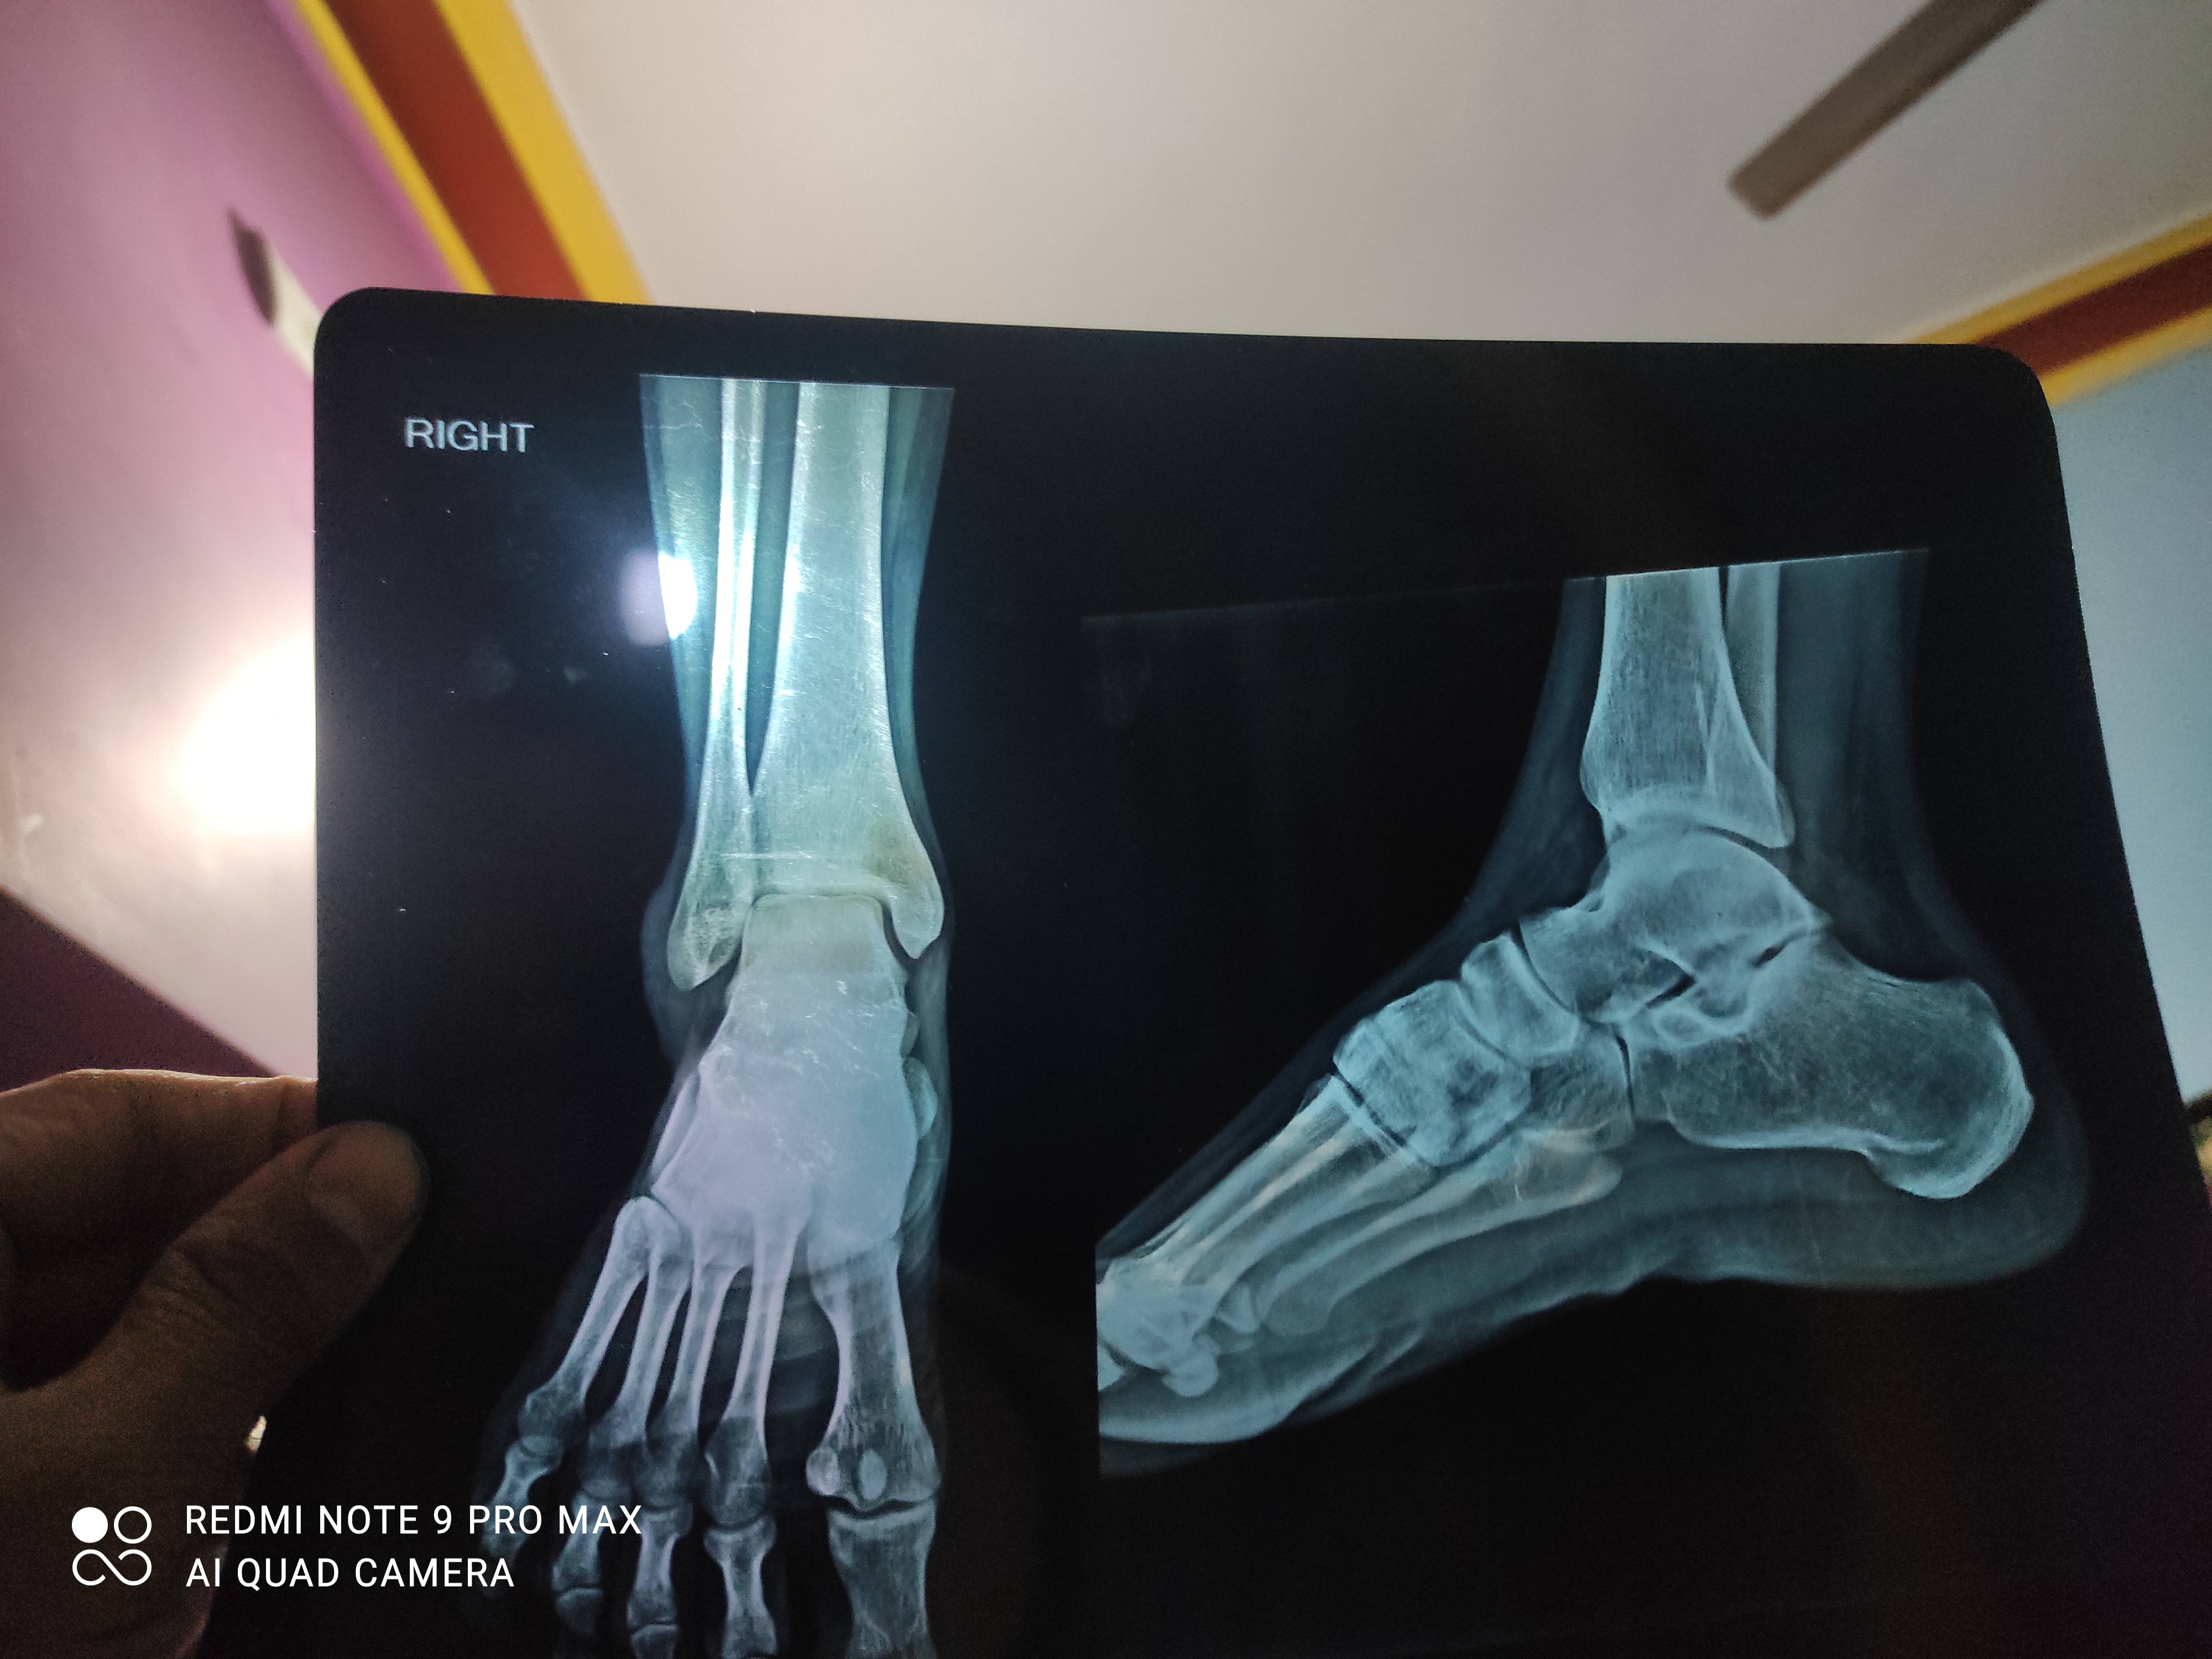

guarantee. Let me tell you when you go to the doctor and the doctor gets your X-Ray done... what do they see in it? Firstly, the X-Ray to be done for the knee replacement has to be done in a standing position. Because, only in a standing position, will I come to know, how badly is the cartilage damaged actually? Let's see this X-Ray of a patient done today. It’s an X-ray of both the left knee and the right knee. The left knee is not so damaged. You can see there is a gap between both the bones. The gap between this bones is more, and here it is less... So, this means that it is 2nd stage of

Arthritis. And if you look at this side... On this side, the gap is more and on this side, the gap is almost

closed... So, this knee demands a replacement today. This means, if your condition is like this, then there is a need for knee replacement. The second thing that we check is if we draw a straight line, how much has the knee bent inwards... Can you see? The knee is not straight, but an angle hascome. The leg has turned inwards...and this too can be covered in Knee replacement. The first thing you should see is how little the gap is left in the knee. Many people understand that the gap increases. Friends, the gap does not increase, the cartilage wears out... If the washer between the bones wears out then the bones get closer. Now look here, this is normal and here the cartilage has

worn out so much... Here, the beak-like extension of bone is called osteophyte. The creation of osteophytes also proves how the knee has worn out. Now, that the cartilage has worn out and bones are touching each other... Now see, bone is touching the bone, there is no gap. The patient is having